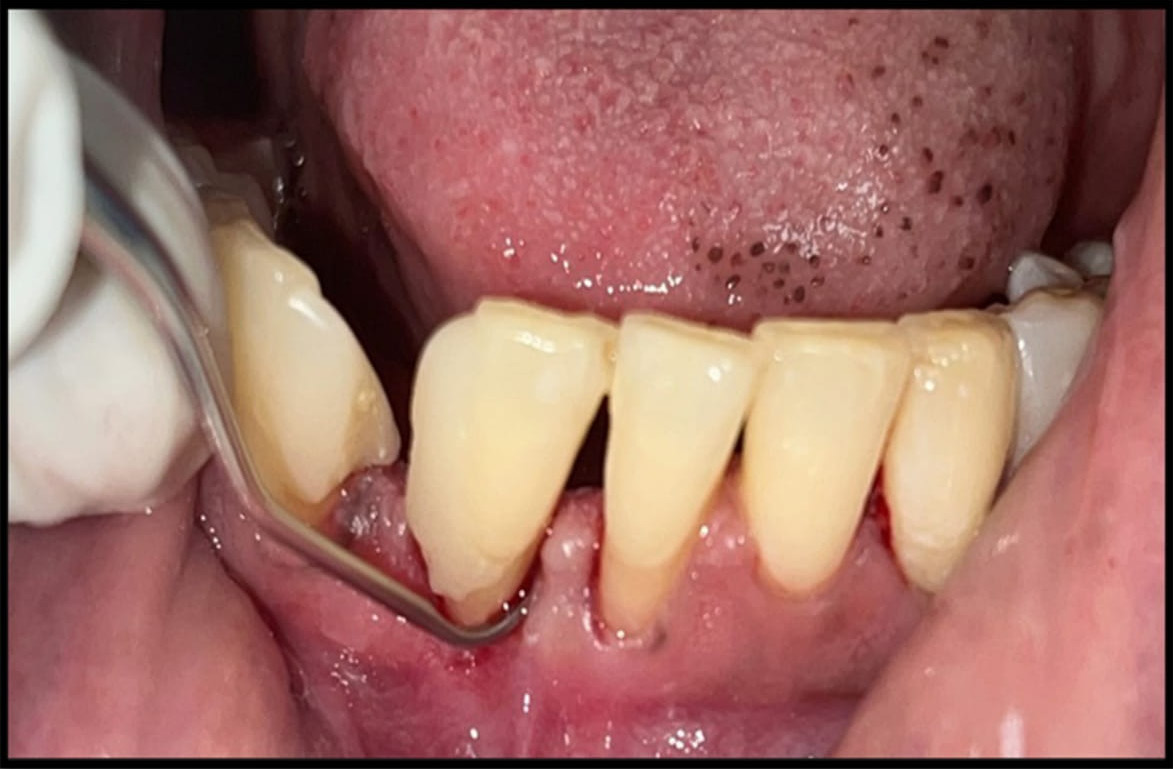

The flowchart of the study is presented in Figure 1. The participants were divided into 3 groups according to the American Academy of Periodontology (AAP) 2017 Classification of Periodontal and Peri-Implant Diseases and Conditions.21 Subjects with GI ≤ 1, PD ≤ 3 mm and BoP ≤ 10% were categorized as periodontally healthy (group 1). Patients with GI > 1, PD ≥ 3 mm and BoP ≥ 10% were diagnosed with gingivitis (group 2). Individuals with GI > 1, CAL ≥ 3 mm and PD ≤ 5 mm were classified as having stage II periodontitis (group 3). Group 3 was further subdivided into group 3A (before NSPT) and group 3B (after NSPT), as subjects with stage II periodontitis underwent NSPT i.e., scaling and root planing (SRP) (Figure 2), and were recalled after 12 weeks for the assessment of periodontal health parameters and saliva sample collection.